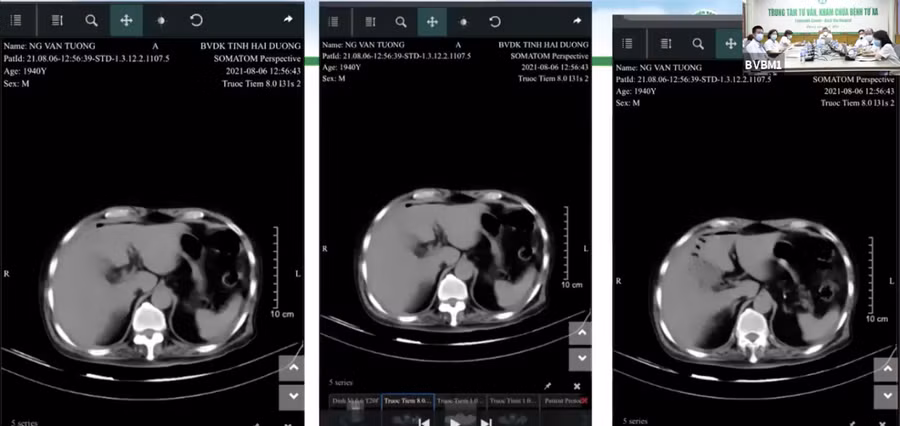

Hội chẩn cùng Bệnh viện Đa khoa Hải Dương

Bệnh nhân Nguyễn Văn T (81 tuổi), nhập viện ngày 6/8. Đau bụng, tiền sử dùng corticoid kéo dài. 4 ngày trước vào viện, bệnh nhân đau bụng vùng hạ sườn phải, sau đó lan toàn bụng kèm nôn, bí trung đại tiện, chán ăn, sốt nhẹ 37,5 - 38 độ C.

Chẩn đoán viêm phúc mạc do thủng tạng rỗng. Xử trí kháng sinh, giảm đau, đảm bảo huyết động, phẫu thuật, cấp cứu. Ổ bụng nhiều dịch trắng lẫn giả mạc,

Chuyên gia chẩn đoán hình ảnh Lại Thu Hương: Dịch quanh gan, khí tự do ở bụng. Bệnh nhân không có tiền sử đái đường, nhưng đường máu cao.

Chuyên gia phẫu thuật tiêu hoá Nguyễn Thành Kiên: Chỉ định mở túi mật lấy sỏi không thực sự hợp lý. Chủ yếu là vấn đề hồi sức sau này.

Theo TS.BS Bùi Thị Giang, bệnh nhân áp xe, nghiện rượu hoặc tiểu đường nguyên nhân là do Crxl. Điều trị kháng sinh có tác dụng với Crxl. Có dấu hiệu viêm phúc mạc muộn do áp xe gan vỡ, phải đánh giá sốc nhiễm khuẩn. Bù dịch 300ml trên cân nặng. Sau đó, bù 1 tiếng. Khi chẩn đoán sốc nhiễm khuẩn, bù dịch và truyền vận mạch nhanh.

GS Nguyễn Gia Bình cho rằng, bệnh nhân đái tháo đường và hay uống rượu. Cần xem nước tiểu, xét nghiệm khí máu.... nhiều lần một ngày. Dịch tinh thể hay cân bằng đã có bằng chứng. Tốc độ truyền dịch phụ thuộc vào mức độ thiếu của bệnh nhân. Cải thiện vi tuần hoàn phải dựa vào lactat.